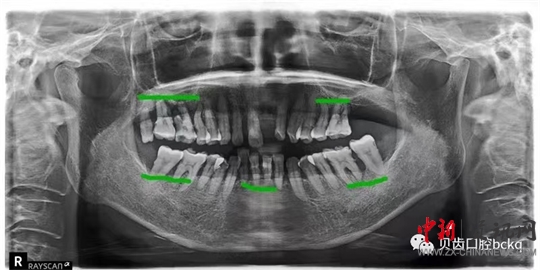

下面這兩張x光片是比較典型的牙周炎的影像資料。該患者的全口所有牙齒都出現(xiàn)了不同程度的松動(dòng);颊攥F(xiàn)在感覺(jué)無(wú)法用牙齒咀嚼。坦白地講,牙周炎發(fā)展到這種程度,很多時(shí)候醫(yī)生也束手無(wú)策了。為了保留更多的牙槽骨,醫(yī)生回不得不拔掉哪些嚴(yán)重松動(dòng)的患牙。